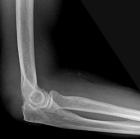

77 year old WM with one year history of right elbow mass with ulceration of the skin, tingling in right small finger also noted

Zoom image: Radiological image Radiological image.